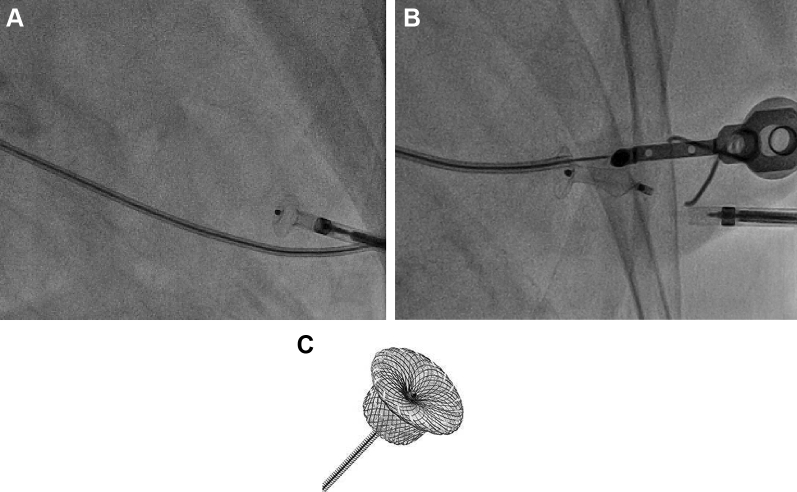

Fig 4.

Closure of percutaneous transapical (TA) puncture site with occluder device. Closure of the TA access site is achieved with an Amplatzer Duct Occluder (C; Abbott Vascular, Santa Clara, Calif) by deploying the device in the apical left ventricle and pulling the disk against the apical wall (A). Once adequate seal of the left ventricular apex is achieved, the device is released (B). Routine ventriculography is then performed to confirm adequate closure of the ventriculotomy.

A number of closure devices designed for percutaneous TA closure are under investigation, some with CE mark.7, 8, 9 These devices achieve TA closure in various ways, including sutured and suture-less techniques. None of the TA closure devices are currently available in the United States. Therefore, our standard practice is to use the Amplatzer Duct Occluder 6/4 for closure of the TA site (Fig 4). We use the same size occluder device for all small-bore (<9F) TA punctures. The “cap” of the device is 10 mm. This cap is pulled back to the wall of the left ventricular apex. The “6” in the size refers to the diameter in millimeters of the device below the cap, and the “4” refers to the size of the tapered distal end in millimeters. The device is 7 mm long. It is designed for closure of a patent ductus arteriosus. When the device is used for this purpose, it is delivered from the pulmonary artery across the patent ductus arteriosus and into the aorta. The cap is then deployed in the aorta and pulled back against the aortic wall. The rest of the device is pulled back until the 4-mm portion of the device is deployed in the pulmonary artery. When it is used for the TA puncture site, the cap of the device rests in the left ventricular cavity and is pulled back against the apical wall. The waist of the device elongates to fill the track created by the sheath through the myocardium. The precise size of the hole in the myocardial wall is difficult to estimate because the puncture is performed while the apex is in motion. Therefore, we have elected to use the 6/4 size device. We have closed many TA punctures with this method and have experienced >90% success with this technique.